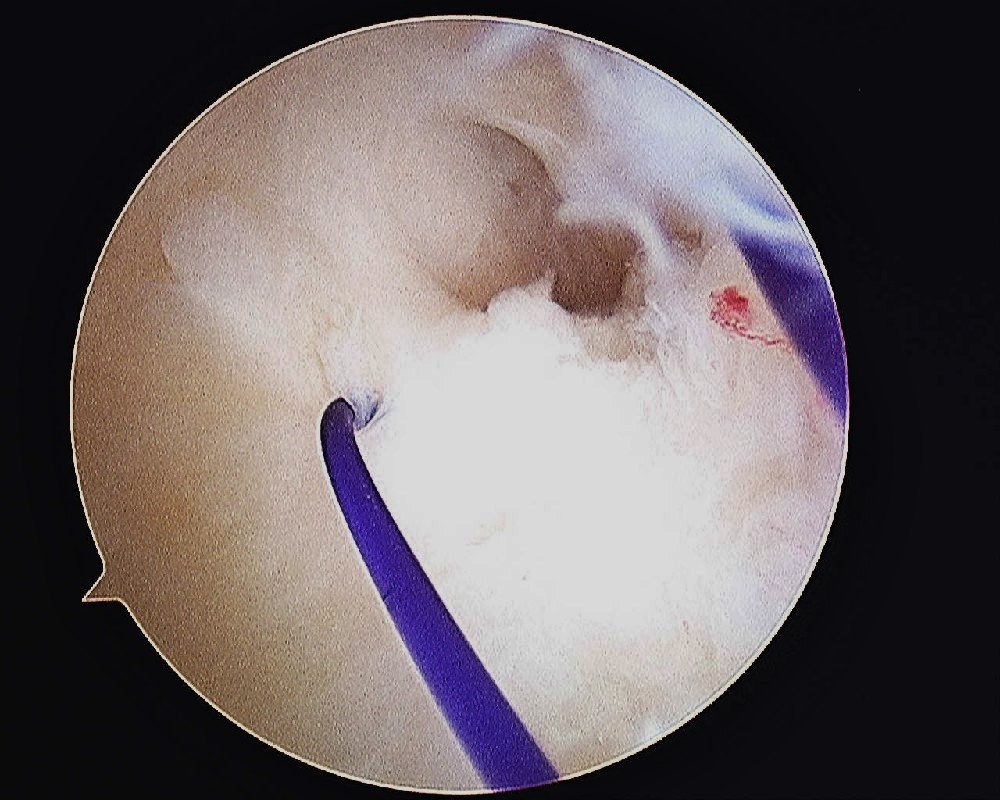

- TFCC Tear – Palmer Type IB

A PDS 3/0 suture is passed into the joint and retrieved through the 4/5 portal using a small arthroscopic grasper